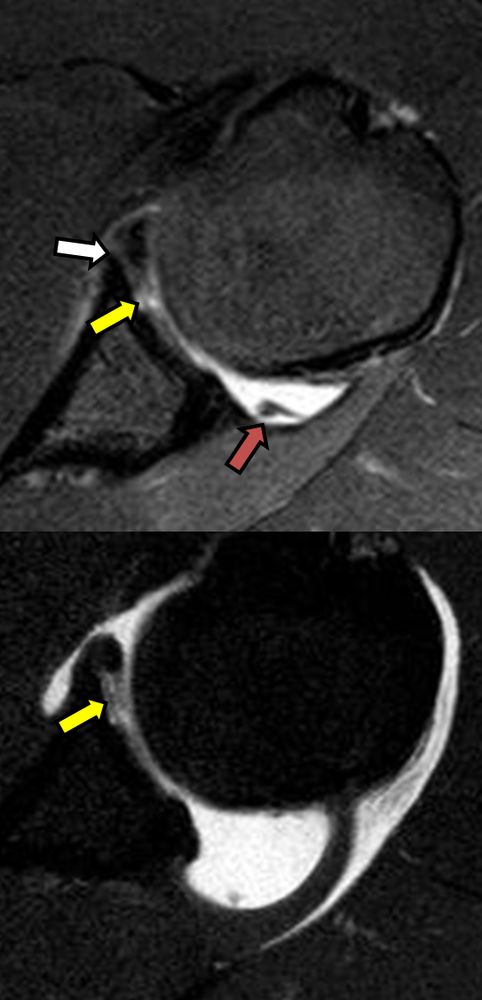

Είναι μια ελάχιστα επεμβατική απεικονιστική μέθοδος που επιτρέπει τη λεπτομερέστερη διερεύνηση του εσωτερικού των αρθρώσεων. Η ασφαλής έγχυση σκιαγραφικού εντός της άρθρωσης υπό ακτινολογική καθοδήγηση και η ακόλουθη απεικόνιση της άρθρωσης με αξονική ή μαγνητική τομογραφία (ή και με συνδυασμό των μεθόδων) αποσαφηνίζει βλάβες του χόνδρου και κακώσεις-ρήξεις συνδέσμων και τενόντων με υψηλή ακρίβεια, συμβάλλοντας σημαντικά στο λεπτομερή χειρουργικό σχεδιασμό.